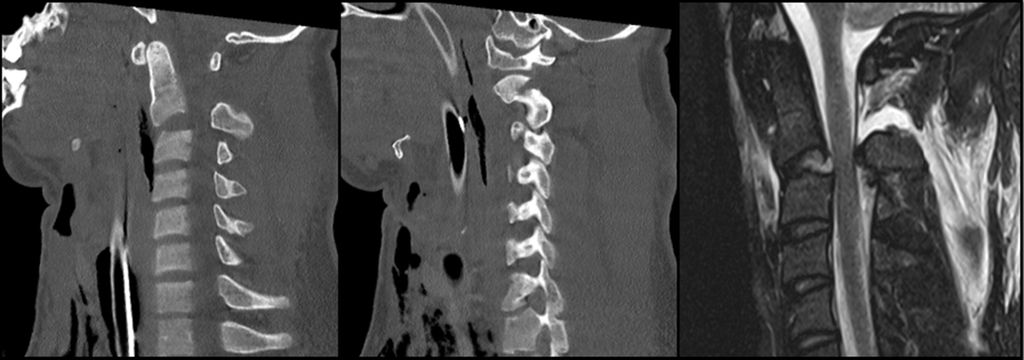

Abb. 1: CT und MRT eines pädiatrischen Patienten mit einer Typ-I-AOD und atlantoaxialer Dislokation nach Verkehrsunfall

AOD stellt die schwerste Verletzungsform im kraniozervikalen Bereich dar und ist für etwa 6–10% aller tödlichen Verletzungen der Halswirbelsäule verantwortlich. Sie tritt in über 30% der tödlichen Fälle nach Verkehrsunfällen auf und zeichnet sich durch eine hohe Letalität aus.5 Der häufigste Verletzungsmechanismus bei der kraniozervikalen Dislokation ist eine Hyperextension infolge stumpfer Gewalteinwirkung. Dabei kommt es häufig zum Riss der Membrana tectoria. Aufgrund des disproportionalen Verhältnisses zwischen Kopf und Körper sind pädiatrische Patient:innen bei Verkehrsunfällen mit hoher Geschwindigkeit besonders gefährdet. Atlantookzipitale Dissoziationen werden traditionell nach der Klassifikation von Traynelis et al.6 in drei Typen eingeteilt: Typ I beschreibt eine anteriore Verschiebung des Okziputs relativ zum Atlas, Typ II eine longitudinale Dislokation und Typ III eine posteriore Verschiebung des Okziputs gegenüber dem Atlas. Die aktuelle Harborview-Klassifikation erlaubt im Vergleich zum oberen Klassifikationssystem eine detailliertere Bewertung der Operationsindikation, da sie auf MRT-Befunden basiert und insbesondere den Grad der Dislokation berücksichtigt. Sie unterscheidet drei Verletzungstypen; TypI stellt eine stabile Verletzung dar, bei der häufig lediglich eine unilaterale Schädigung der kraniozervikalen Bänder vorliegt. In diesen Fällen ist eine konservative Behandlung in der Regel erfolgreich. Ab Typ II wird eine dorsale okzipitozervikale Fusion unter Verwendung von Plattensystemen empfohlen.